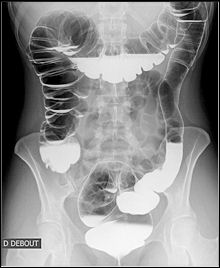

Image

radiologique normale du colon en double de contrast

: les haustrations sont en bien visible meme en face

anterieure et posterieure . |

Colon ascendant et

descendant sont bien voyait en double de contrast

|